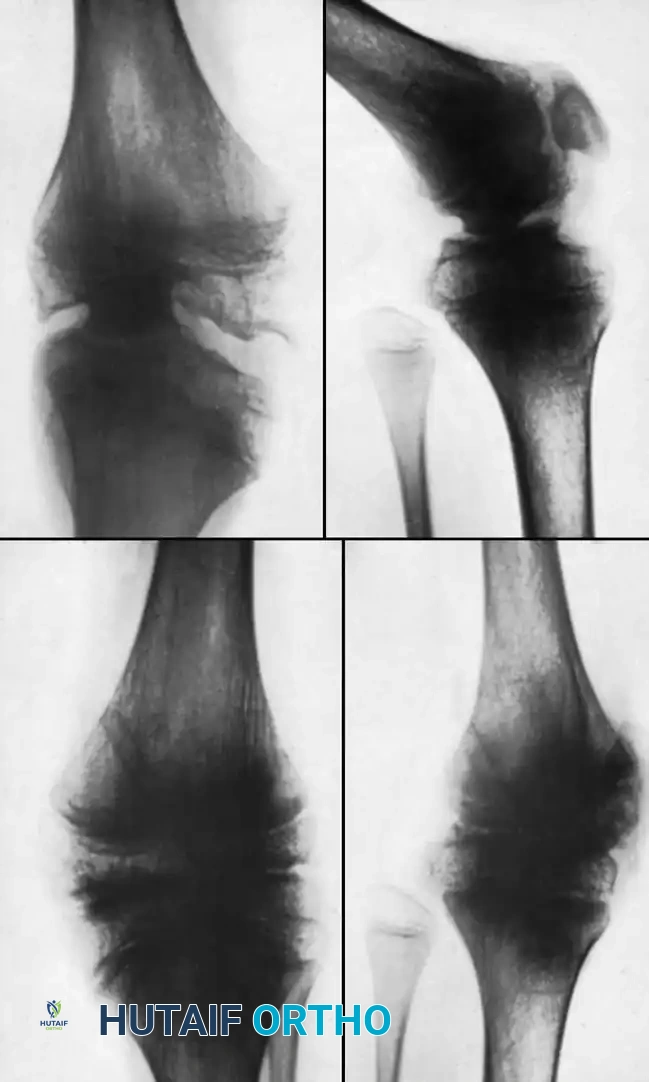

تصلب وتشوه الركبة بعد التهاب المفاصل القيحي وتصحيحها جراحيا

في هذه العملية المعقدة، يتم فصل العظام الملتحمة وإعادة تشكيلها لتتطابق في وضع مستقيم. في حالات التشوه الشديد جداً، يتم تصحيح الوضع على مراحل لتجنب شد الأوعية الدموية والأعصاب، باستخدام أجهزة التثبيت الخارجي الدائرية.

مخطط يوضح عملية قطع العظم داخل المفصل لعلاج تصلب الركبة